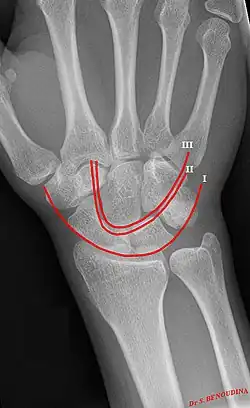

Gilula's lines are three arcs drawn on an AP radiograph of the wrist used to assess the alignment of the carpal bones.[1]

There should be no step-off in the contour of the lines when drawn on a normal wrist.

First arc | running along the proximal convexity of the scaphoid, lunate and triquetrum |

Second arc | running along the distal concavities of the scaphoid, lunate and triquetrum |

Third arc | running along the proximal curvatures of the capitate and hamate |